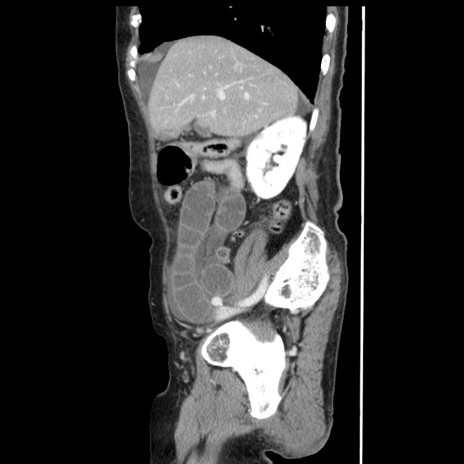

冠状断像

【症例】80歳代女性

【主訴】腹痛

【現病歴】8時間前から腹痛あり来院。

【既往歴】糖尿病、脂質異常症、子宮体癌にて子宮全摘術

【身体所見】意識清明・会話良好だが腹痛で苦悶様、全腹部にわたって反跳痛と圧痛あり

【データ】WBC 13600、CRP 0.14、LDH 224、CK 90